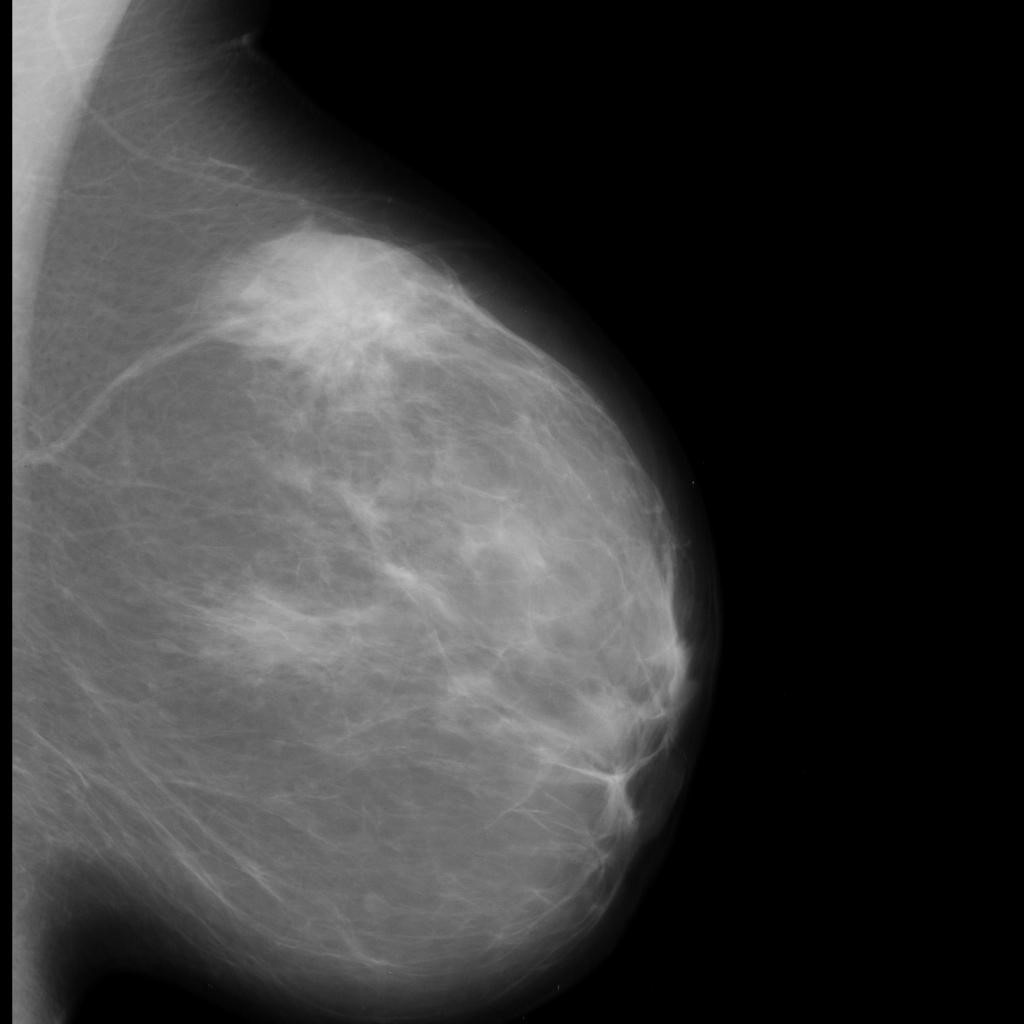

benign

malignant